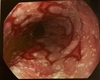

Exemplos de ________.

Tumores avançados de esôfago